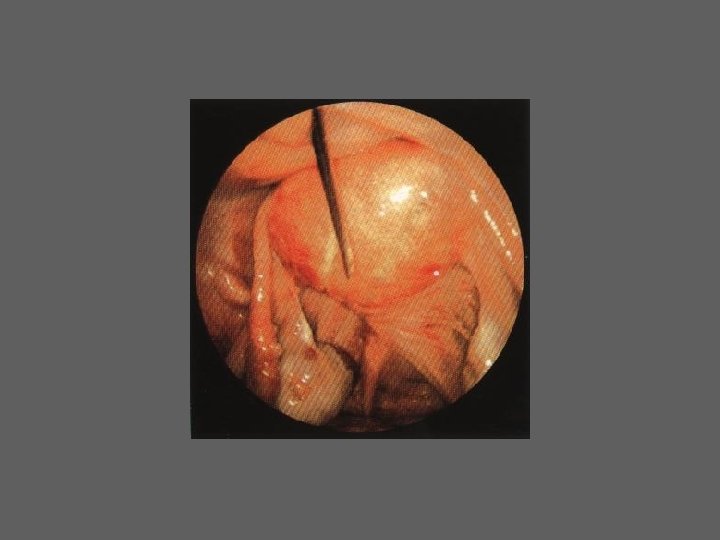

CELIOSCOPIA - INDICAÇÕES – Estudo e tratamento da infertilidade – Em todas as situações de sintomatologia obscura ou diversificada em que o exame ginecologico não revela uma patologia evidente: • Gravidez tubar • Doença inflamatória pélvica aguda • Algias pélvicas inespecíficas e crónicas – Realização de intervençõe cirurgicas

CELIOSCOPIA - COMPLICAÇÕES – As mais significativas são ligadas à anestesia e à absorção de CO 2 – Hemorregias (parede; intraabdominais) – Perfuração de visceras – Enfisema extraperitoneal – Queimaduras intestinais – Embolia gasosa – Problemas anestésicos – Celioscopia “falhada” – Infecções